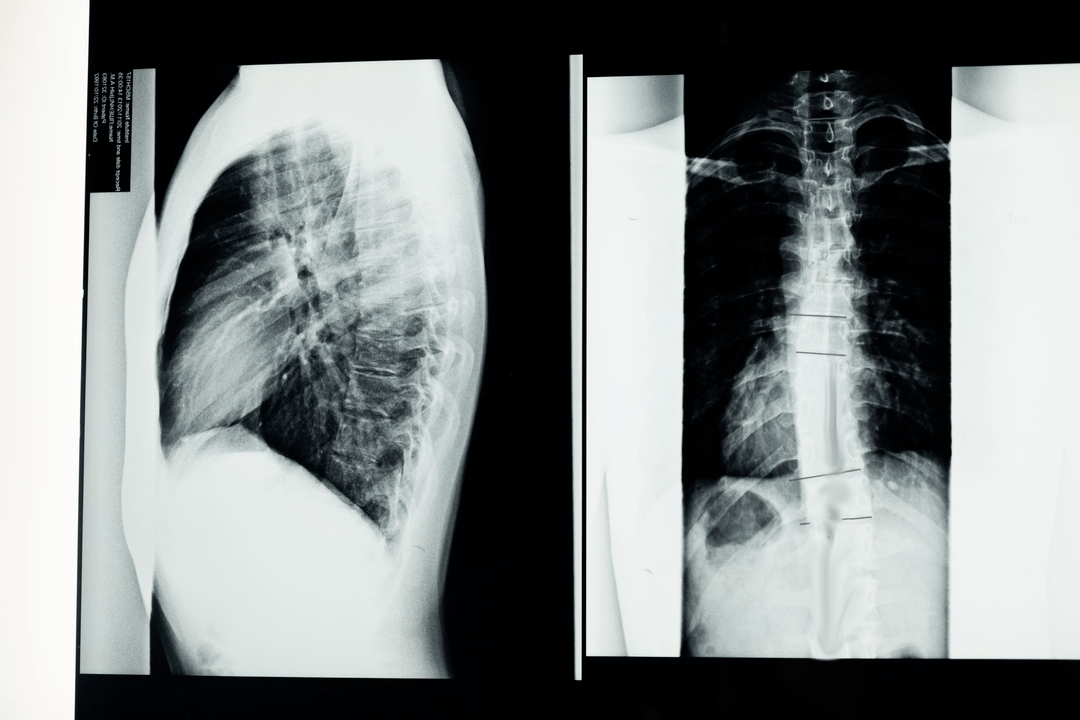

Before starting diagnostic studies, the neurologist collects the patient's medical history and carefully studies his complaints.Osteochondrosis has common symptoms with several other diseases, so it is important to differentiate the pathologies.X-ray studies will help confirm the diagnosis of osteochondrosis: X-ray, myelography and computed tomography.

An X-ray study allows you to take an X-ray image of the spine or part of it.In this way, the doctor can determine the location affected by the disease.For clarity, we will explain how osteochondrosis can be determined by x-ray: the image will show a narrowing of the intervertebral disc, the presence of bone growths (osteophytes) or a change in the shape of the spinal segment.